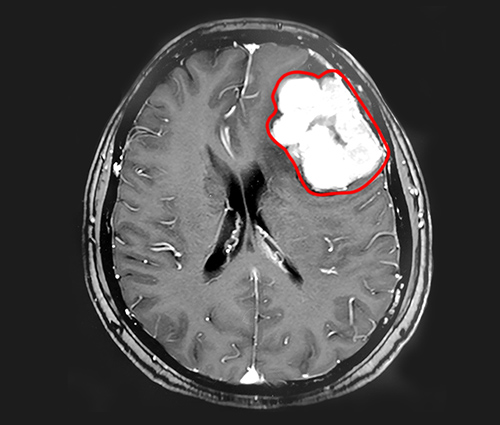

▲MRI影像显示,患者左侧额叶有体积较大的肿瘤

在蓝十字,程阿姨的头颅核磁共振影像显示,患者左侧额叶有巨大团块状异常信号,大小约5.5*4.3*4.8cm,临近的左侧侧脑室受压变窄。在这个肿瘤周围,还有多枚体积较小的肿瘤,具有脑膜瘤的典型特征。